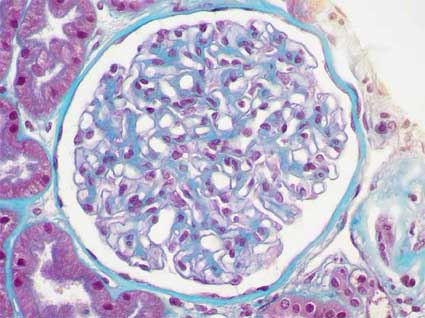

Las lesiones más iniciales son hipertrofia glomerular, expansión mesangial leve (matriz) y engrosamiento de las paredes capilares, estos cambios son más evidentes con microscopía electrónica. Al progresar las lesiones hay aumento, también, de la celularidad mesangial; este incremento llega hasta la formación de nódulos en el penacho. Los nódulos son de tamaño variable en un mismo glomérulo y afectan de una manera heterogénea los diferentes glomérulos (glomeruloesclerosis nodular diabética). Los nódulos son conocidos como nódulos de Kimmelstiel-Wilson. Son esféricos, eosinofílicos, con un área central acelular y pueden estar rodeados por un anillo celular. Tiñen azul o verde con el tricrómico y son positivos con las tinciones de PAS y plata-metenamina. Los nódulos son de dos tipos morfológica y patogénicamente: unos son pequeños, mesangiales (o intercapilares) y los otros son grandes con aspecto laminado en la tinción de plata (Figuras 1, 2, 3, 4). Los grandes se formarían a partir de capilares glomerulares dilatados (microaneurismas, >35 micras de diámetro) que generarían lesión en la pared capilar, trombosis y proliferación de matriz colágena (Stout LC, et al., Hum Pathol; 24:77-89, 1993 [PubMed link]) (Figuras 3 y 4). Los pequeños se ven como una acentuación redondeada de la matriz mesangial y tiñen más intensamente con el PAS que los nódulos grandes y laminados. La presencia de estos nódulos: grandes y pequeños, algunos laminados, con tamaño y distribución variable en el glomérulo y entre los glomérulos, es "virtualmente patognomónica" de ND, aunque hay descritos casos idiopáticos con histología similar (Markowitz GS et al., Hum Pathol 33:826-35, 2002 [PubMed link]; Chang CS, et al., Clin Nephrol 64:300-4, 2005 [PubMed link]; Navaneethan SD, et al., J Nephrol 18:613-5, 2005 [PubMed link] [Free full text]). Los nódulos vistos en la enfermedad por depósitos de cadenas ligeras pueden ser parecidos, pero más homogéneos en tamaño y distribución y tiñen más débilmente, o son negativos, con la tinción de plata; los nódulos de la amiloidosis no tiñen con la plata y son positivos para rojo congo. La IF también ayuda en el diagnóstico diferencial.

Figura 1. Un glomérulo con lesiones nodulares de Kimmelstiel-Wilson. Los nódulos más pequeños pueden ser más celulares y los más grandes tienden a ser acelulares en el centro y rodeados por zonas más celulares. Alrededor de estos nódulos se ven capilares, a veces adoptando un aspecto en guirnalda (como en los tres nódulos señalados con flechas); en algunos casos vemos microaneurismas alrededor de nódulos. Note la variabilidad de tamaño de los nódulos (H&E, X400).

Figura 5. En muchos de los glomérulos la lesión de ND se limita a engrosamiento mesangial (global o segmentario) y engrosamiento difuso de las paredes capilares. Note en esta microfotografía la prominencia de los tallos mesangiales. Además hay aumento del grosor de la basal de la cápsula de Bowman. (Tricrómico de Masson, X400).